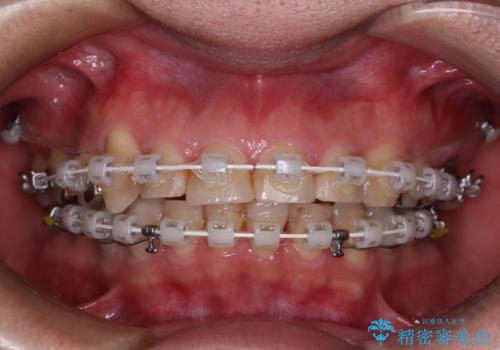

銀歯を白くしたい 一緒に矯正治療も行ない美しい口腔内に

- 近医にて下顎奥歯の抜歯が必要と言われたとのことで来院された患者様です。

診察の結果、奥歯は左右ともに抜歯が必要な状態でした。

他の銀歯も気になっており、セラミックにしたいとの要望があり、詳しくお話をすると、デコボコの歯ならびも整えたいとのことでした。

抜歯が必要な歯は事前に抜歯をし、その後ワイヤー装置にて歯列矯正を行い、途中でインプラントを埋入し、オールセラミッククラウンにて補綴治療を行うこととしました。

矯正治療にやや時間がかかりましたが、歯列はきれいに整い、気になっていたむし歯や銀歯は自然な色合いに仕上がりました。